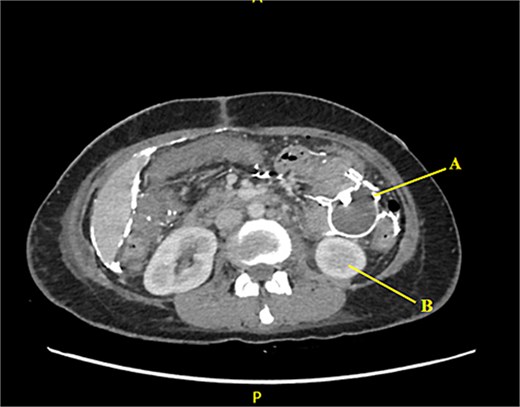

Contrast-enhanced CT of the abdomen and pelvis revealed extensive barium extravasation outlining the peritoneal cavity, accompanied by pneumoperitoneum (Fig. 3). Two barium-outlined, walled-off intra-abdominal collections were identified: one located anterior to the lower pole of the left kidney and the other in the pelvis, anterior to the rectum (Figs 4 and 5). Due to significant barium-related imaging artifacts, the precise site of bowel perforation was not identified. A diagnosis of peritonitis secondary to barium spillage was established, with associated intra-abdominal collections.

Barium-lined intra-abdominal collection (A) anterior to the left kidney (B).